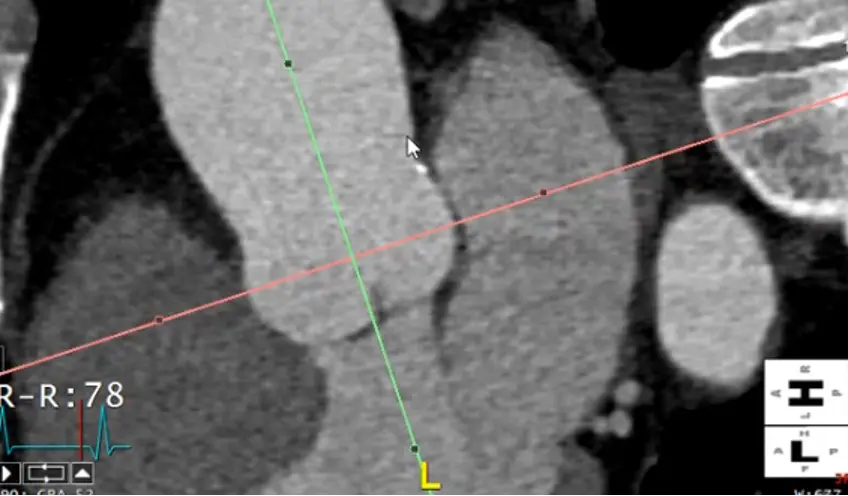

Measure at the widest segment

- The widest segment (typically) is at the mid-aorta at the level of the main pulmonary artery (MPA)

- Same as above, drag your crosshairs to the desired level and adjust to be perpendicular to the artery wall in the coronal and sagittal views. Line up the blue/green line to be in the center/parallel to the long axis of the aorta at that level.

- In the axial view, the âtrue short axisâ should appear like a circle

Alt+Dto auto-measure- Right click and

Captureto add this to theSeries List

Measure the proximal descending thoracic aorta

- Note: the proximal descending thoracic aorta begins immediately distal to the great vessels (not when the aorta physically starts descending), i.e. after the takeoff of the L subclavian artery

- Line things up in two of the views. In the example Adam showed, he lined it up in the axial and sagittal views and made the measurement in the coronal view.

- Note: the shape of the proximal descending thoracic aorta will not be perfectly circular.